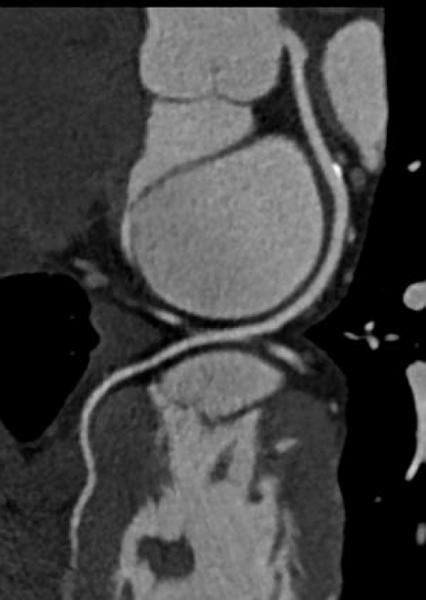

Coronary computed tomography angiography (CCTA) is a noninvasive tool that can be used for identifying myocardial ...

The next big advancement in cardiac imaging is likely to be computed tomography (CT) perfusion imaging. This enables one ...

As catheter-based, minimally invasive procedures expand rapidly beyond treatment of the coronary arteries into all areas ...